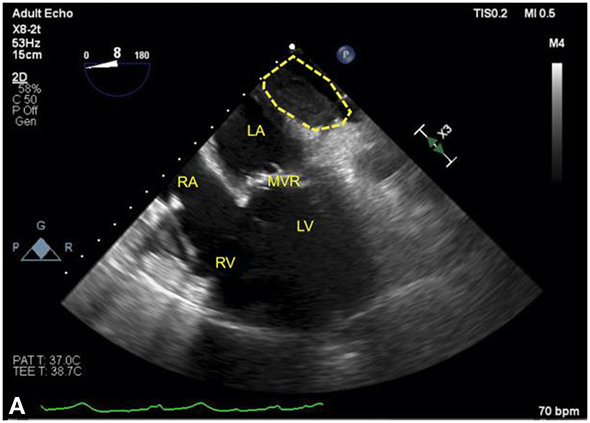

Figure 12.3.: Acute Regional Pericardial Effusion: Left Atrial Compression.

Acute regional pericardial effusion: left atrial compression. A and B show an example of regional pericardial effusion posterior to the heart, compressing the left atrium (LA), is shown. The heart is shown in a midesophageal four-chamber view, with (A) rotated leftward to center the view on the localized pericardial effusion (dotted line). In both views, the left ventricle (LV) is partially obscured by shadowing artifact from a bioprosthetic mitral valve replacement (MVR). A. The LA is partially compressed by the effusion. B. The same heart following decompression, showing restoration of LA size, is seen. Agitated blood can be seen in the right atrium (RA) and right ventricle (RV) during intravenous fluid administration.